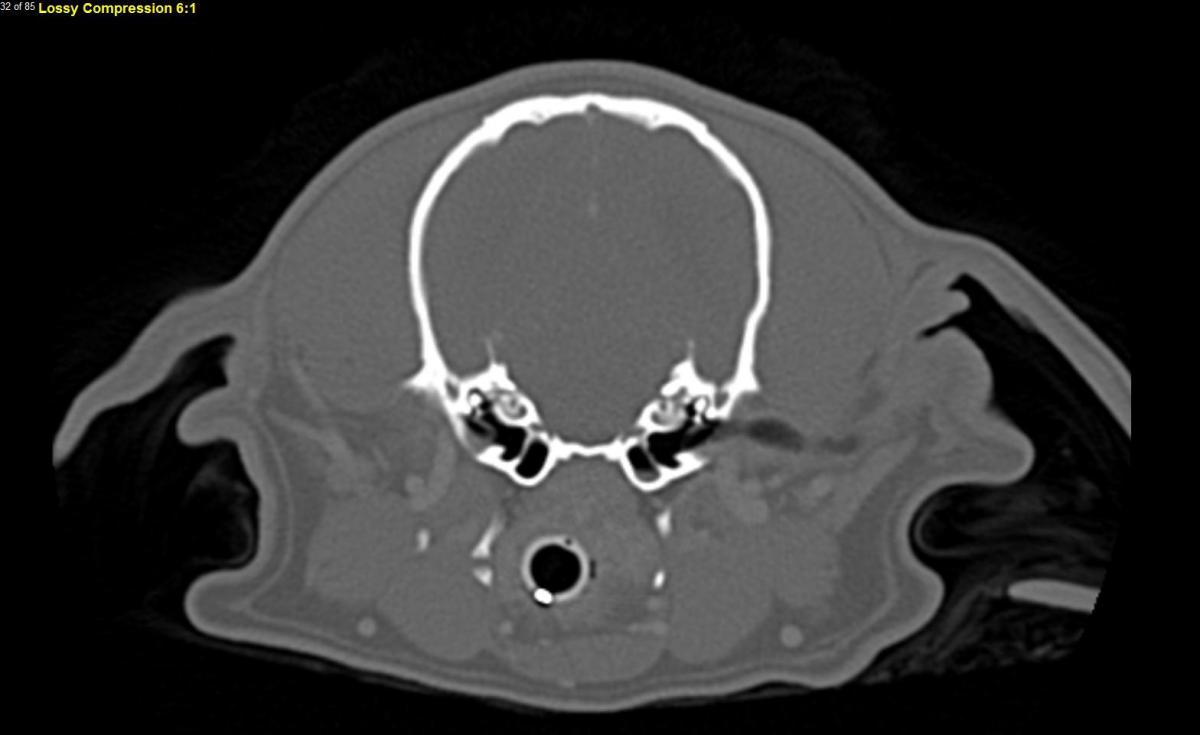

Q. This image is taken from a 4 year old female intact Cavalier King Charles Spaniel. This dog was diagnosed at a 2.5 years of age with caudal occipital malformation syndrome (COMS) and syringohydromyelia (SM): asymptomatic, grade 2 cerebellar impingement, grade 2c syringohydromyelia. In the last 2 weeks, she has developed the signs seen in the photo below.

Interpret this CT image:

A. This is an axial post-contrast computed tomography image of the canine skull taken at the level of the tympanic bullae. There is a small amount of soft tissue opacity material in the ventral aspect of the left tympanic bulla and a possible slight defect of the tympanic membrane at the dorsal aspect on that same side. There is not overt lysis or other changes in the bony structures. The primary differential is infectious otitis media, though early primary secretory otitis media, injury after ear cleaning, neoplasm, and central brain lesion cannot be fully ruled out. Myringotomy with cytology and cultures is recommended following the CT scan to try to confirm infection.